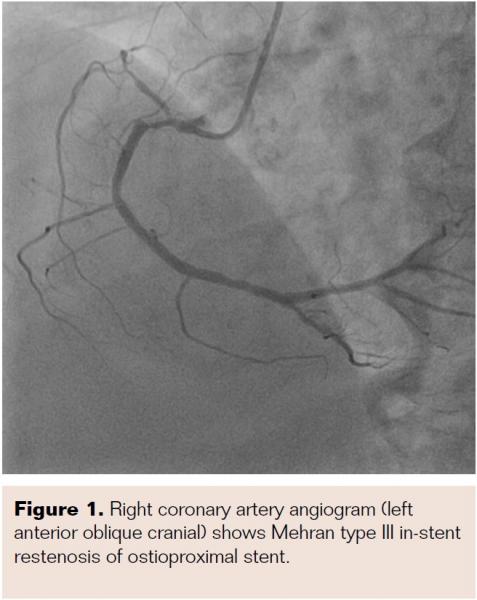

He was admitted and was managed for acute coronary syndrome – unstable angina. He was managed as per guideline-directed medical treatment and was later taken for coronary angiogram after written informed consent. A precatheterization profile was performed and a radial approach with a 5 Fr Tiger catheter (Terumo) was chosen. The left coronary system showed no significant lesions, but Mehran type III in-stent restenosis (ISR) was noted in the ostioproximal RCA stent (Figure 1). Accordingly, the decision was made to proceed with repeat PCI, and when the 6 Fr Judkins right 3.5 guide catheter (Medtronic) was exchanged and manipulated, the patient reported severe chest pain. Echocardiogram showed ST elevation in inferior leads. The check angiogram showed ostial right coronary total occlusion (Figure 2A), so the RCA was quickly wired with a 0.014" balance middle weight floppy wire (Abbott Vascular) and the ostioproximal lesion was predilated with a 2 mm x 10 mm Sprinter Legend semicompliant balloon (Medtronic) (Figure 2B). Postdilatation cine showed a longitudinal homogenous opacity moving from the proximal RCA and embedded into the distal RCA, causing TIMI 0 flow (Figures 2C and 2D). Because the first differential for TIMI 0 flow was thrombotic occlusion, our strategy was to disintegrate the thrombus via balloon manipulation. After failure on multiple attempts, thrombosuction with a 6 Fr, 140 cm Thrombuster II (Kaneka Medix Corp.) was performed and a pale soft tissue was retrieved (Figure 3A). Imaging post thrombosuction showed clearing of the ISR and TIMI III flow across the RCA (Figure 4). Histopathology of the retrieved tissue reported endothelial cells with intermittent muscle cells (Figure 3B). The ostioproximal RCA was stented with a 3 mm x 18 mm Xience Pro everolimus-eluting coronary stent (Abbott Vascular) and TIMI III flow was noted with resolution of chest pain and ECG changes (Figure 5). The patient was closely monitored for 48 hours and was discharged.